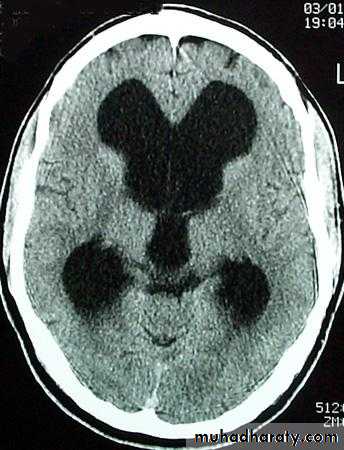

Hydrocephalous

2 types

Obstructive ( non – communicating )

Craniophyrengioma

Medulloblastoma

Ependymoma

Aquiduct stenosis , comments cause of obstruction being congenital in nature .

Non –obstructive ( communicating )

No obstruction of the ventricular pathway , but the absorption of the csf at the level of arachnoids' granulation is occluded secondary to lodge by blood clot or inflammatory cell or infection post meningitis most commonly to occur post SAH .